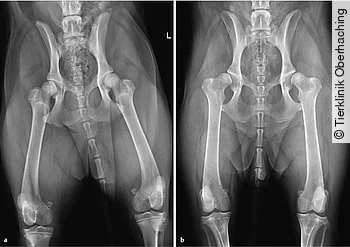

Bei einem dysplastischen Gelenk werden durch die nach dorsal gerichtete Subluxationstendenz der mediale Anteil des Femurkopfes sowie der dorsale Acetabulumrand überlastet, sodass deren Ossifikation verzögert ist [6], während der ventromediale Anteil des Acetabulums und der laterale Anteil des Femurkopfes zu früh ossifizieren [7]. Hieraus resultieren eine Abflachung des Acetabulums sowie eine Unterentwicklung des dorsalen Acetabulumrandes [13]. Die Knorpelflächen werden in den überlasteten Regionen abgerieben, bis subchondraler Knochen freiliegt, der als Reaktion vermehrt sklerosiert [7]. [Abb. 1] zeigt die weit fortgeschrittenen degenerativen Veränderungen der HD eines älteren Patienten. Im Vergleich hierzu bildet [Abb. 4 b] die initiale Subluxationstendenz eines jung adulten Hundes vor der Entstehung degenerativer Veränderungen ab. Die ausgeprägte Coxarthrose in [Abb. 1] ist als Folge der Laxizität und Inkongruenz der Hüftgelenke zu werten. Grundsätzlich können degenerative Veränderungen des Hüftgelenks auch z. B. infolge eines Traumas (Luxation, Fraktur), Osteochondrose o. ä. ohne zugrundeliegende HD entstehen [14].

Weltweit existieren unterschiedliche Standards zur Röntgendiagnose der HD als Basis züchterischer Selektion. Systeme weisen Schwachpunkte auf, die einer effektiveren Ausmerzung von HD aus der Hundepopulation im Wege stehen. Nicht alle Zuchtverbände fordern z. B. verpflichtend eine Allgemeinanästhesie, Röntgenaufnahmen am wachen Patienten verringern jedoch die diagnostische Qualität erheblich [66], [67] ([Abb. 4]). Der in Deutschland primär angewandte Standard wird durch die Fédération Cynologique Internationale (FCI) festgelegt.